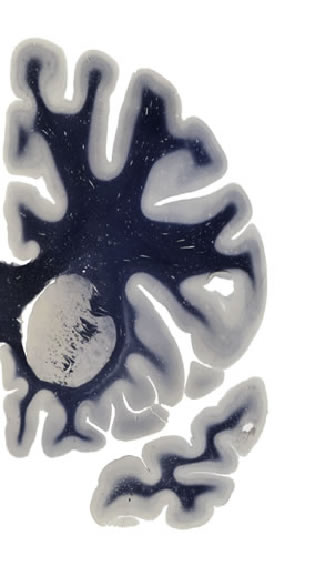

Frontal sections (Nissl) from the Atlas Brain: Gallery Slice Single

-14,8 mm

Slice ID: r2-0395

Plate NR: 12

Position: -14,8 mm